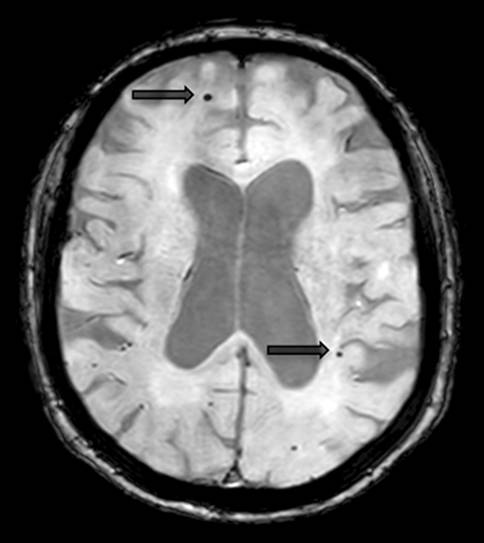

Lacunes and Virchow-Robin spaces

Lacunes are deep, small-vessel infarcts with a CSF-like signal on all MRI sequences (illustrated in Fig. 5). In contrast, Virchow-Robin spaces are enlarged perivascular spaces usually due to volume loss of the surrounding tissue with a predilection for the basal ganglia (illustrated in Fig. 6).

Fig. 6

Virchow-Robin spaces. Illustration of enlarged Virchow-Robin spaces (circles) in the lower aspect of the basal ganglia on both sides on axial T2-weighted images